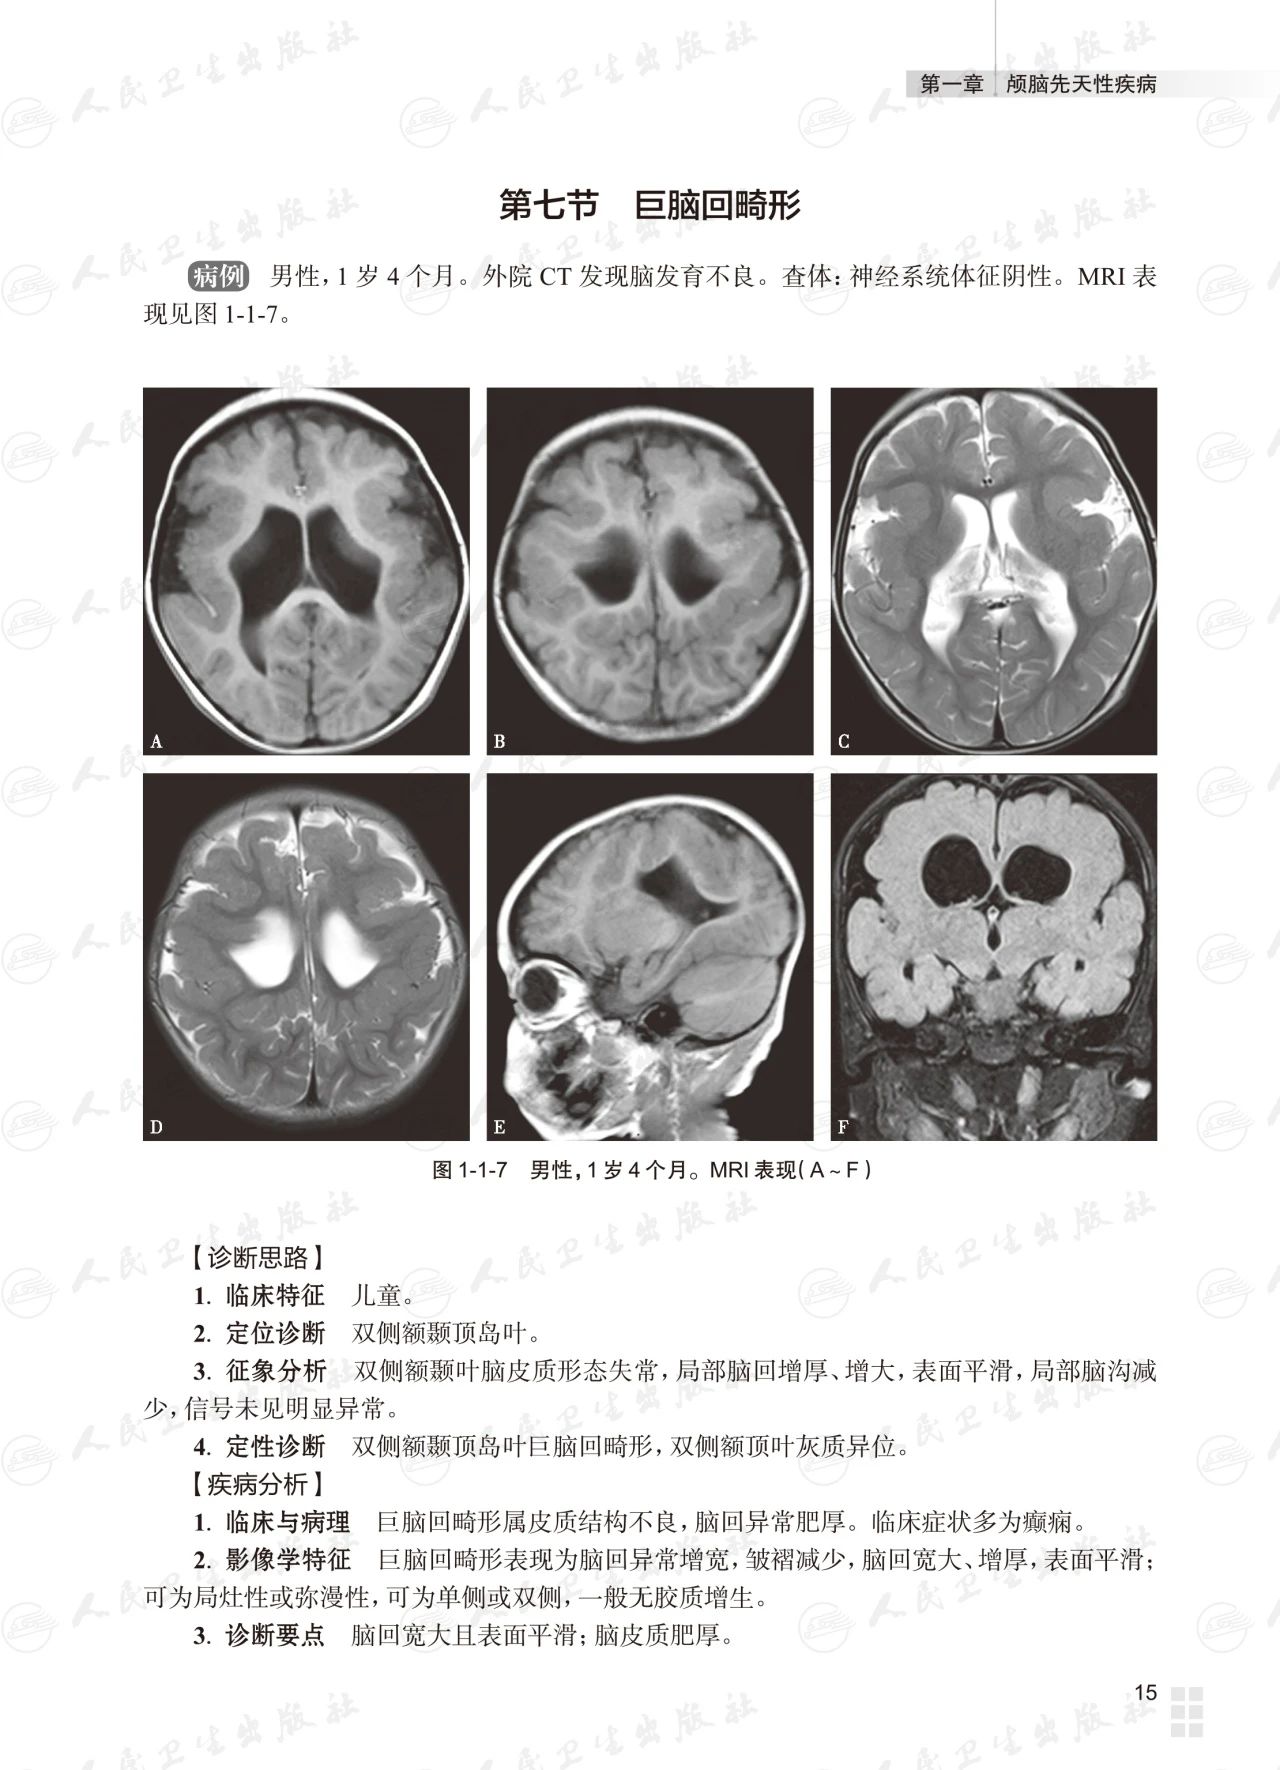

基础篇为常见颅脑疾病多模态磁共振成像典型病例分析,以复习为主,从疾病的临床与病理入手,解析影像学特征,提供影像诊断思路,最终给出诊断要点;